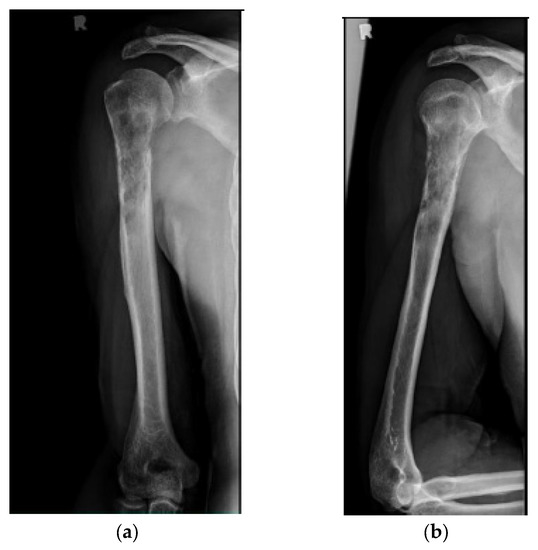

Figure 2.

(a) AP and (b) lateral right humerus radiographs of a 67-year-old male with a mixed lytic sclerotic lesion in the proximal meta-diaphyseal region, with a pathologic fracture from a newly diagnosed metastatic prostate cancer. This was treated by a bone biopsy, followed by a cemented IMN with two proximal inter-locking screws and no distal screw, as shown in the (c) AP and (d) lateral humerus radiographs. Cement was used for augmentation, due to poor proximal humerus bone quality, to support the nail and the inter-locking screws.